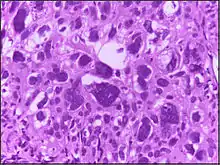

Micrograph showing large cells. H&E stain.

Large cell is a term used in oncology. It does not refer to a particular type of cell; rather it refers to cells that are larger than would be normally expected for that type. It is frequently used when describing lymphoma and lung cancer.